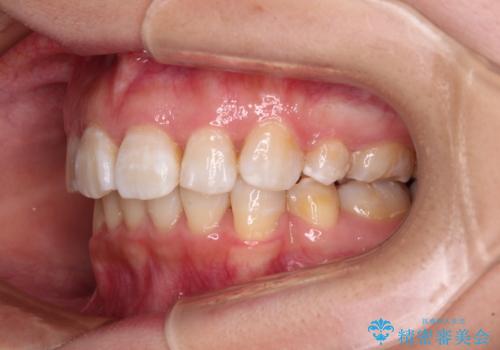

矯正治療終了近くに九州へ引っ越すことになってしまい、なかなか来院することができなくなったため、引っ越してから1年以上の期間が必要となってしまいました。